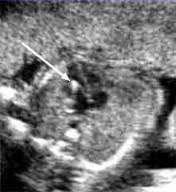

A Review On Techniques For Computer Aided Diagnosis Of Soft Markers For Detection Of Down Syndrome In Ultrasound Fetal Images Biomedical And Pharmacology Journal